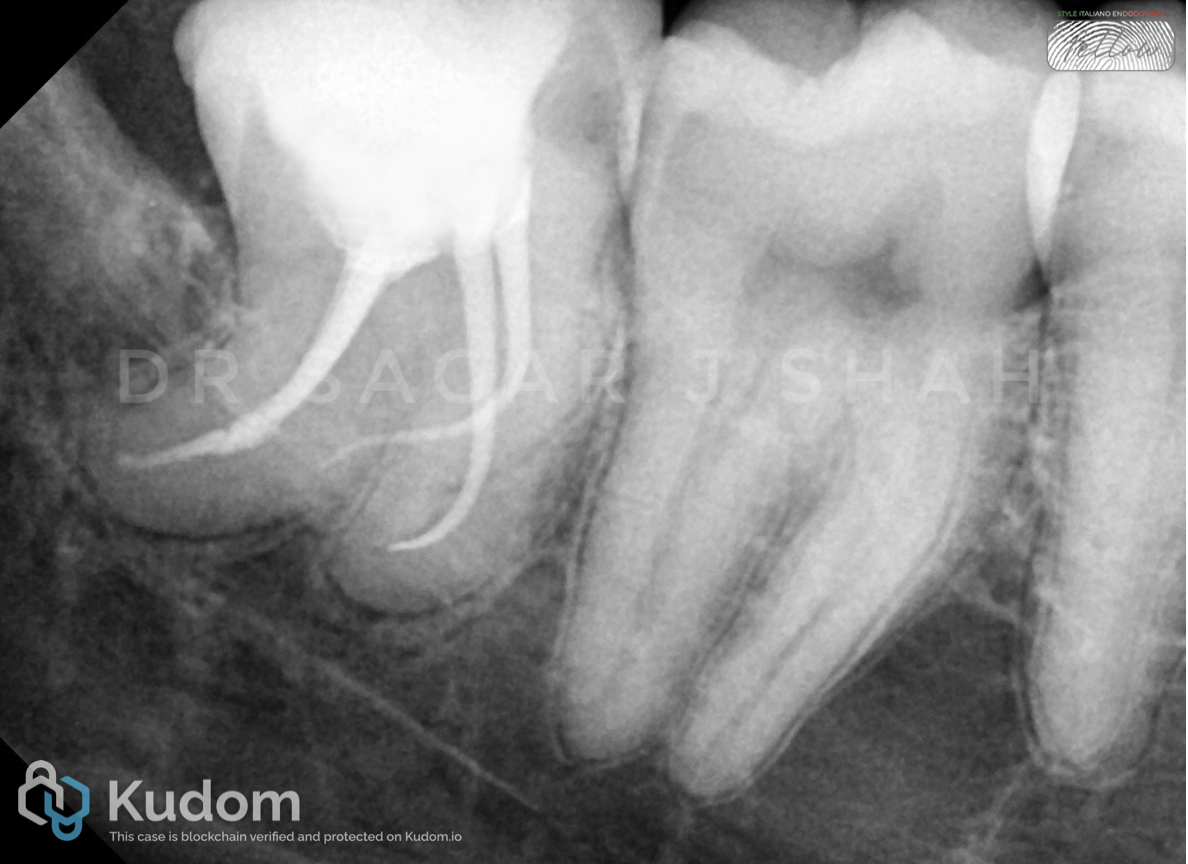

Advances in endodontic materials have influenced contemporary approaches to root canal obturation. A bioceramic sealers possess favorable properties, including biocompatibility, dimensional stability and the ability to form hydroxyapatite, which may enhance sealing root canal spaces. These characteristics have contributed to a shift toward simplified obturation techniques, particularly the single-cone approach. Compared with traditional compaction techniques, this method reduces procedural complexity and clinical time while maintaining an effective seal of the root canal system. For straightforward endodontic cases with adequate cleaning and shaping, simplified obturation protocols using bioceramic sealers have demonstrated predictable clinical outcomes.